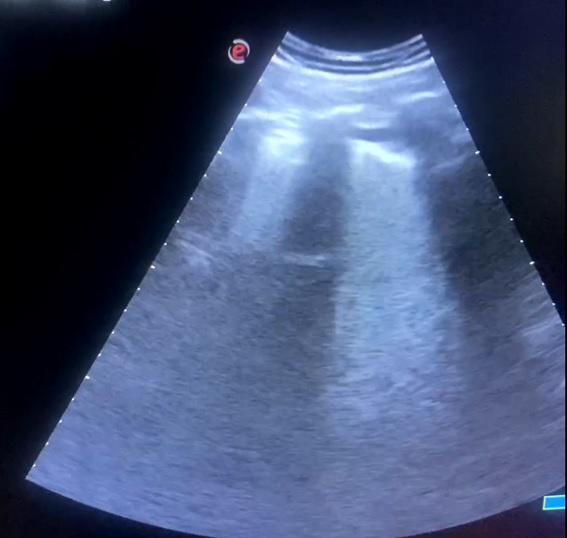

Ecografía pulmonar en AP:

«Líneas B en campos pulmonares izquierdos y consolidación pulmonar en base derecha con mínimo derrame pleural, compatible consolidación infecciosa vs tromboembólica.

Se amplía estudio con ETT que no muestra signos de sobrecarga de ventrículo derecho, y eco Doppler de MMII sin hallazgos de TVP con venas safenas y femorales permeables y colapsables».